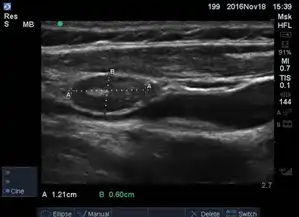

1. - Ultrasound: Can help assess the fluid buildup and rule out other conditions.

1. lymph9